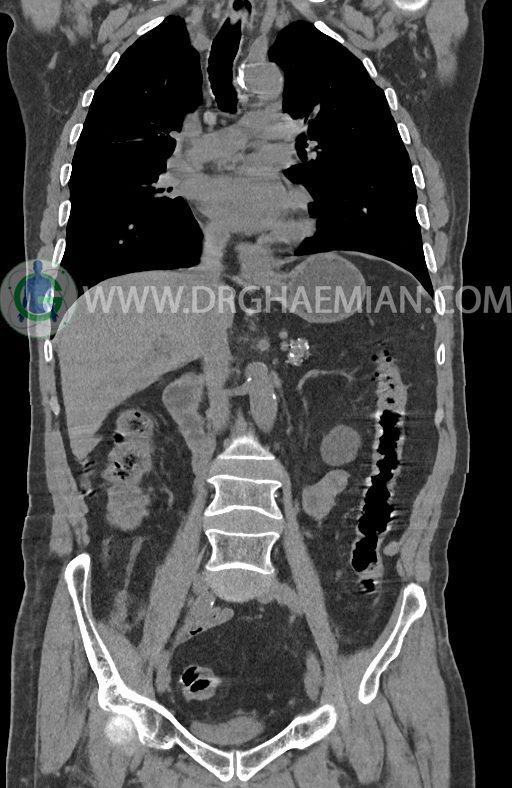

در سی تی اسکن اسپیرال ریه ها و مدیاستن، شکم و لگن با و بدون کنتراست وریدی (مولتی دیدکتور 16 با مقاطع ظریف و بازسازی کرونال) :

–آتروفی نسبی پانکراس همراه با فوکوس های کلسیفیه ی منتشر پارانشیم مطرح کننده ی پانکراتیت مزمن

-CBD بسیار دیلاته (16mm) همراه با دیلاتاسیون مجاری داخل کبدی سنترال بدون شواهد سنگ یا توده در مسیر

–کیست های کورتیکال متعدد هر دو کلیه به بزرگترین قطر 56mm

–پروستات به دیامتر عرضی بزرگ حاوی فوکوس کلسیفیه